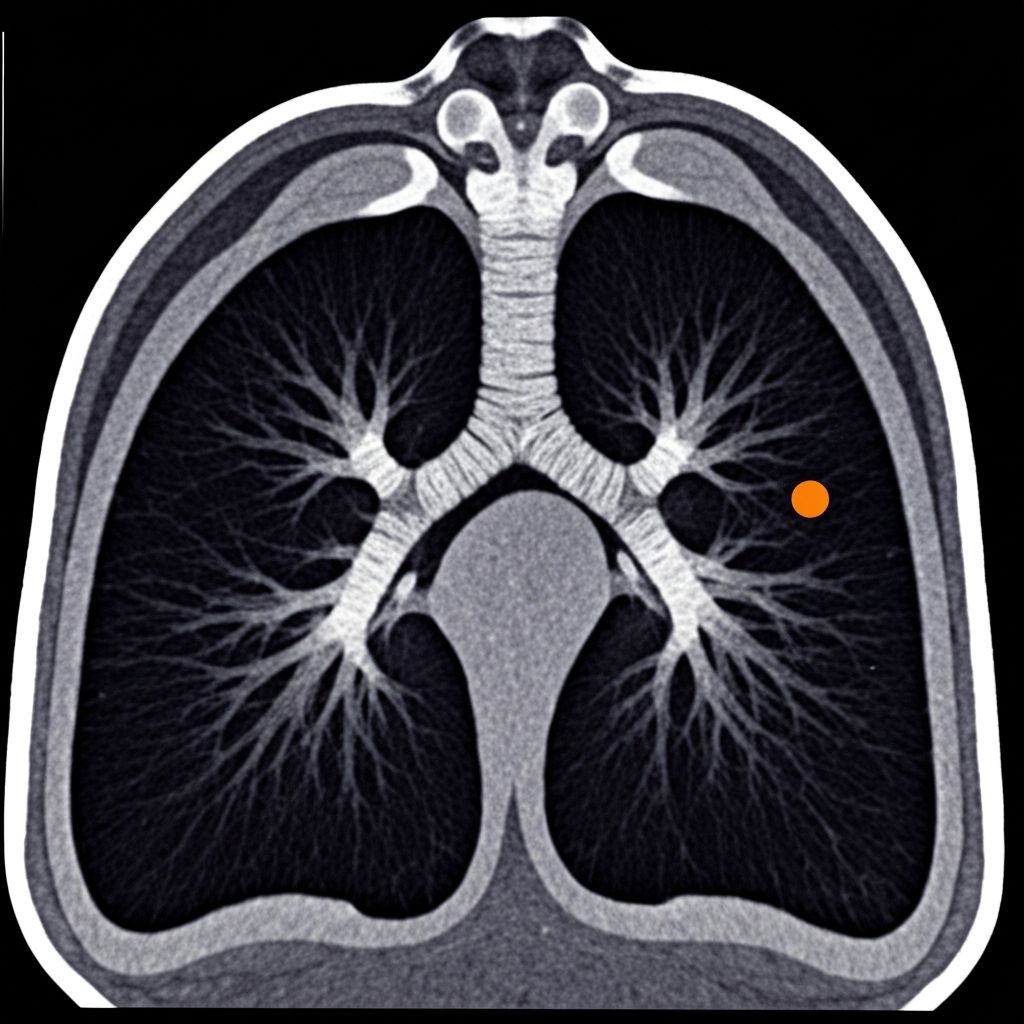

CT CHEST 2025

SLICE 47/128

ZOOM 1.2x